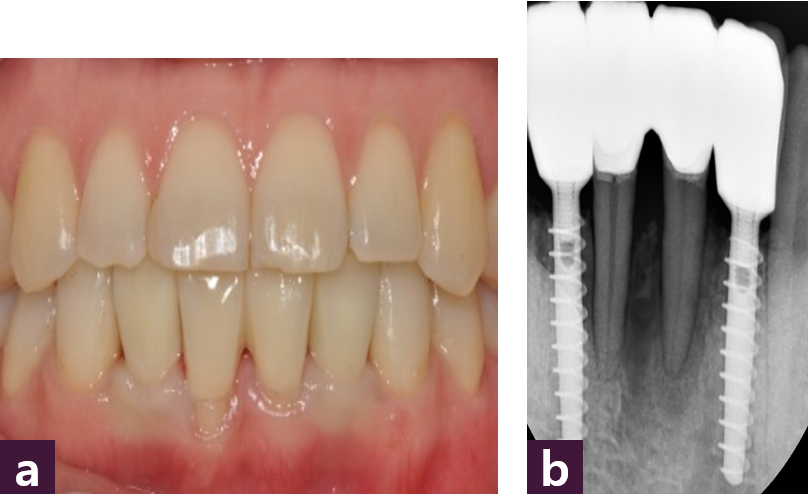

마지막으로 Short Abutment를 사용하여 zirconia cement retained type 최종 보철물을 완성하였다 [그림 11, 12].

최종 보철물 제작 2개월 후 구강 내 사진에서 만족스러운 연조직 치유 양상을 확인할 수 있다 [그림 13].